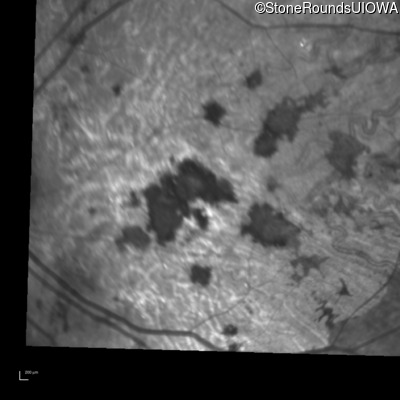

Blue Autofluorescence - Right - 20/150 sc

Exemplar